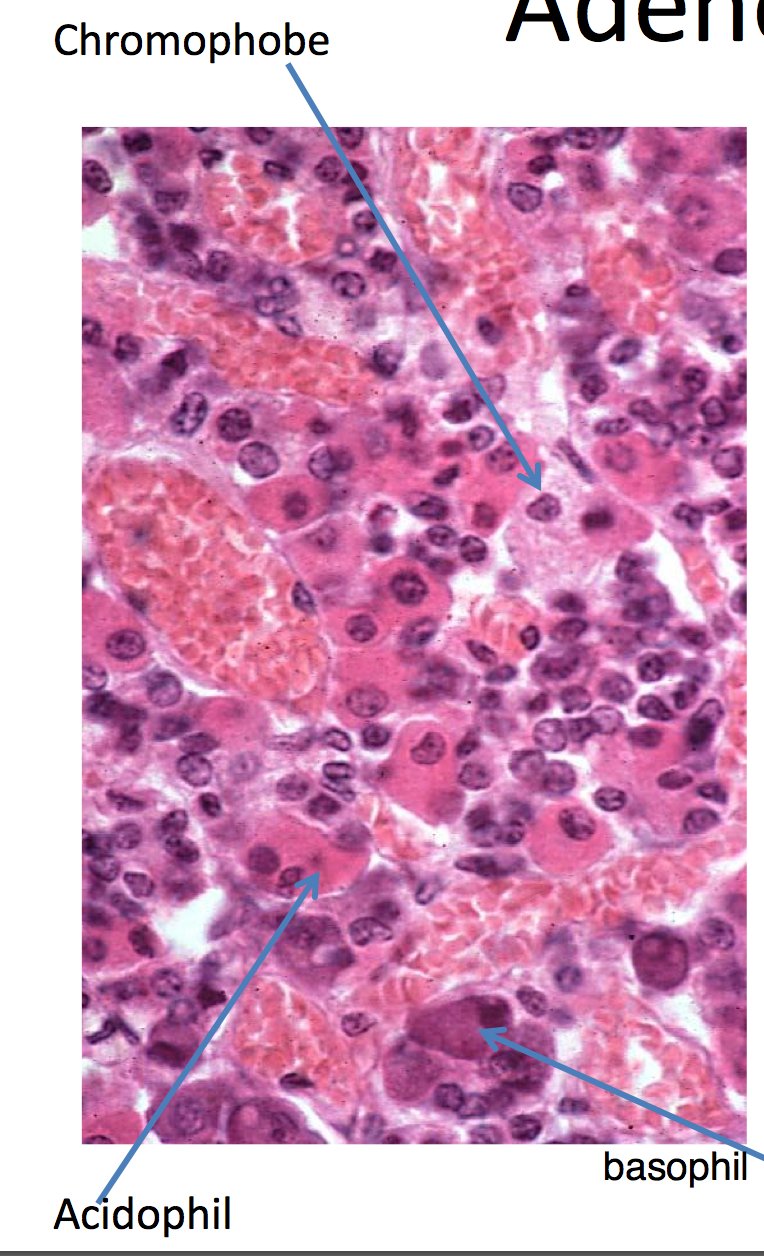

adenohypophysis